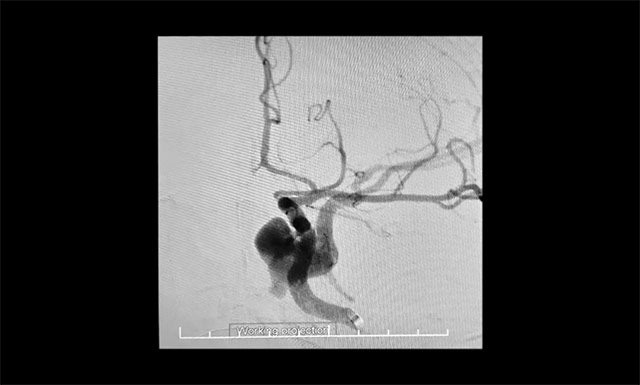

▲ DSA 检查确诊:左侧颈内动脉海绵窦瘘

颈动脉3D造影提示,左侧颈内动脉海绵窦瘘,瘘口位于颈内动脉破裂孔段内后方,瘘口处假性动脉瘤形成,血液向左侧侧裂静脉及左侧岩下窦上方引流,瘘口小,流量大,属于难治性颈内动脉海绵窦瘘。综合患者病情,张琪主任决定实施球囊保护联合封堵手术。该手术手术操作繁琐,技术难度较大、对术者要求很高。